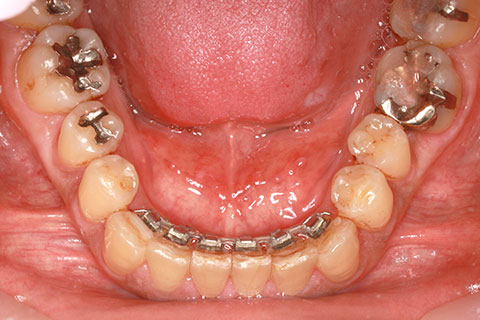

フルリンガル矯正1(上下の歯を舌側矯正で治療)

治療前

治療中

治療後

- 年齢・性別

- 33歳女性

- 治療期間

- 2年0ヶ月

- 抜歯

- 上顎4番抜歯。下顎5番欠損。

- 治療費

- 120万円(税込み)

- 備考

- フルリンガル矯正

- 治療内容

- 上顎前歯の叢生改善および下顎前歯の空隙閉鎖

- 施術の副作用(リスク)

- 装置が裏側について、目視ができないため、しっかりとブラッシングができているかどうかわかりにくい。